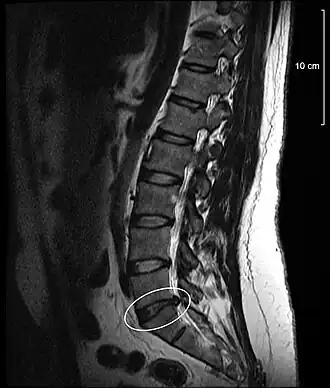

Протру́зия межпозвонко́вого ди́ска — патологический процесс в позвоночнике, при котором межпозвонковый диск выбухает в позвоночный канал без разрыва фиброзного кольца, возникающего при грыже. Чаще всего локализуется в поясничном и реже — шейном отделах. В клинической практике встречается гораздо чаще, чем экструзия.

При протрузии межпозвонкового диска фиброзное кольцо сохраняет целостность, и сдавливание (раздражение) корешков носит интермиттирующий (периодический) характер. Размер выбухания в различных случаях составляет от 1 до 5 мм.